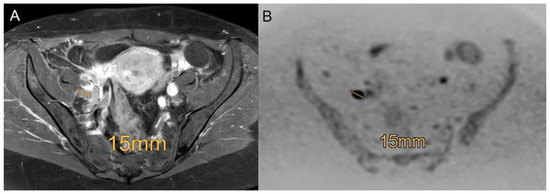

Figure 4. Example of a patient with a FIGO IIIC1 cervical carcinoma with involvement of pelvic lymph nodes using the standard MRI ((A), contrast enhanced transversal T1-weighted scans with fat saturation) and DWIBS (B) with a right-sided 15 mm lymph node metastasis proven by histopathology. Diagnosis is more reliable in DWIBS (B) compared to contrast enhanced transversal T1-weighted scans with fat saturation (A).